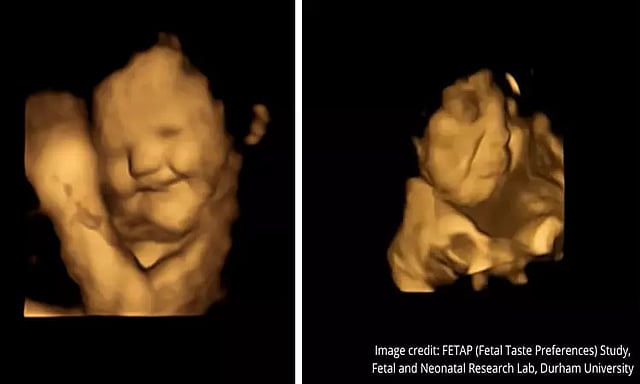

உணவின் சுவையை உணர்ந்து கருவில் இருக்கும் குழந்தைகள் வெளிப்படுத்திய முக பாவனைகளின் புகைப்படங்கள் இணையத்தை ஆக்கிரமித்துள்ளது.

அதாவது தாயின் கருவில் இருக்கும் குழந்தைகள் பல்வேறு உணவின் வாசனைகள் மற்றும் சுவைகளை உணர்ந்து எவ்வாறு முக பாவனைகளை வெளிப்படுத்துகின்றன என்பது தான் அந்த ஆராய்ச்சி.

டர்ஹாம் பல்கலைக்கழக ஆராய்ச்சியாளர்கள் 100 கர்ப்பிணிப் பெண்களிடம் 4டி அல்ட்ராசவுண்ட் பரிசோதனைகளை ஆய்வு செய்தனர். இந்த ஆய்வின் போது 35 கர்ப்பிணி பெண்களுக்கு கேரட் சுவை கொண்ட காப்ஸ்யூல்கள் வழங்கப்பட்டது. அவர்கள் அதை எடுத்துக்கொண்ட 20 நிமிடங்களுக்கு பிறகு கருவில் இருக்கும் குழந்தைகள் மகிழ்ச்சியாக சிரிப்பது அல்ட்ராசவுண்ட் பரிசோதனையில் தெரிய வந்தது.

அதே நேரத்தில் மற்ற 35 கர்ப்பிணி பெண்களுக்கு முட்டைக்கோஸ் போன்ற 'இலை தாவர உணவு' சுவை கொண்ட காப்ஸ்யூல்கள் வழங்கப்பட்டது. இதை அந்த கர்ப்பிணி பெண்கள் சாப்பிட்ட சில நிமிடங்களுக்கு பிறகு அவர்களின் குழந்தைகள் 'அழுகை முகத்துடன்' இருப்பது அல்ட்ராசவுண்ட் பரிசோதனையில் தெரியவந்தது.

இந்த ஆய்வின் போது உணவின் சுவையை உணர்ந்து கருவில் குழந்தைகள் வெளிப்படுத்திய முக பாவனைகளின் புகைப்படங்களை டர்ஹாம் பல்கலைக்கழகம் வெளியிட்டுள்ளது. அந்த புகைப்படங்கள் தற்போது இணையத்தை ஆக்கிரமித்துள்ளது.